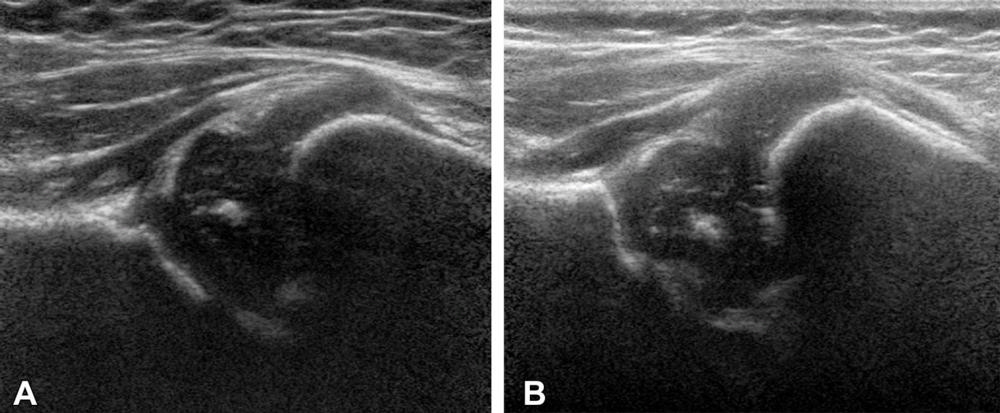

Figure 6. Examples of hip US images acquired with mode 3; no contrast material was used. The presented hips were (A) −1.90 (girl) and (B) +1.49 (girl) standard deviations from the mean shape.

High-res (TIF) version